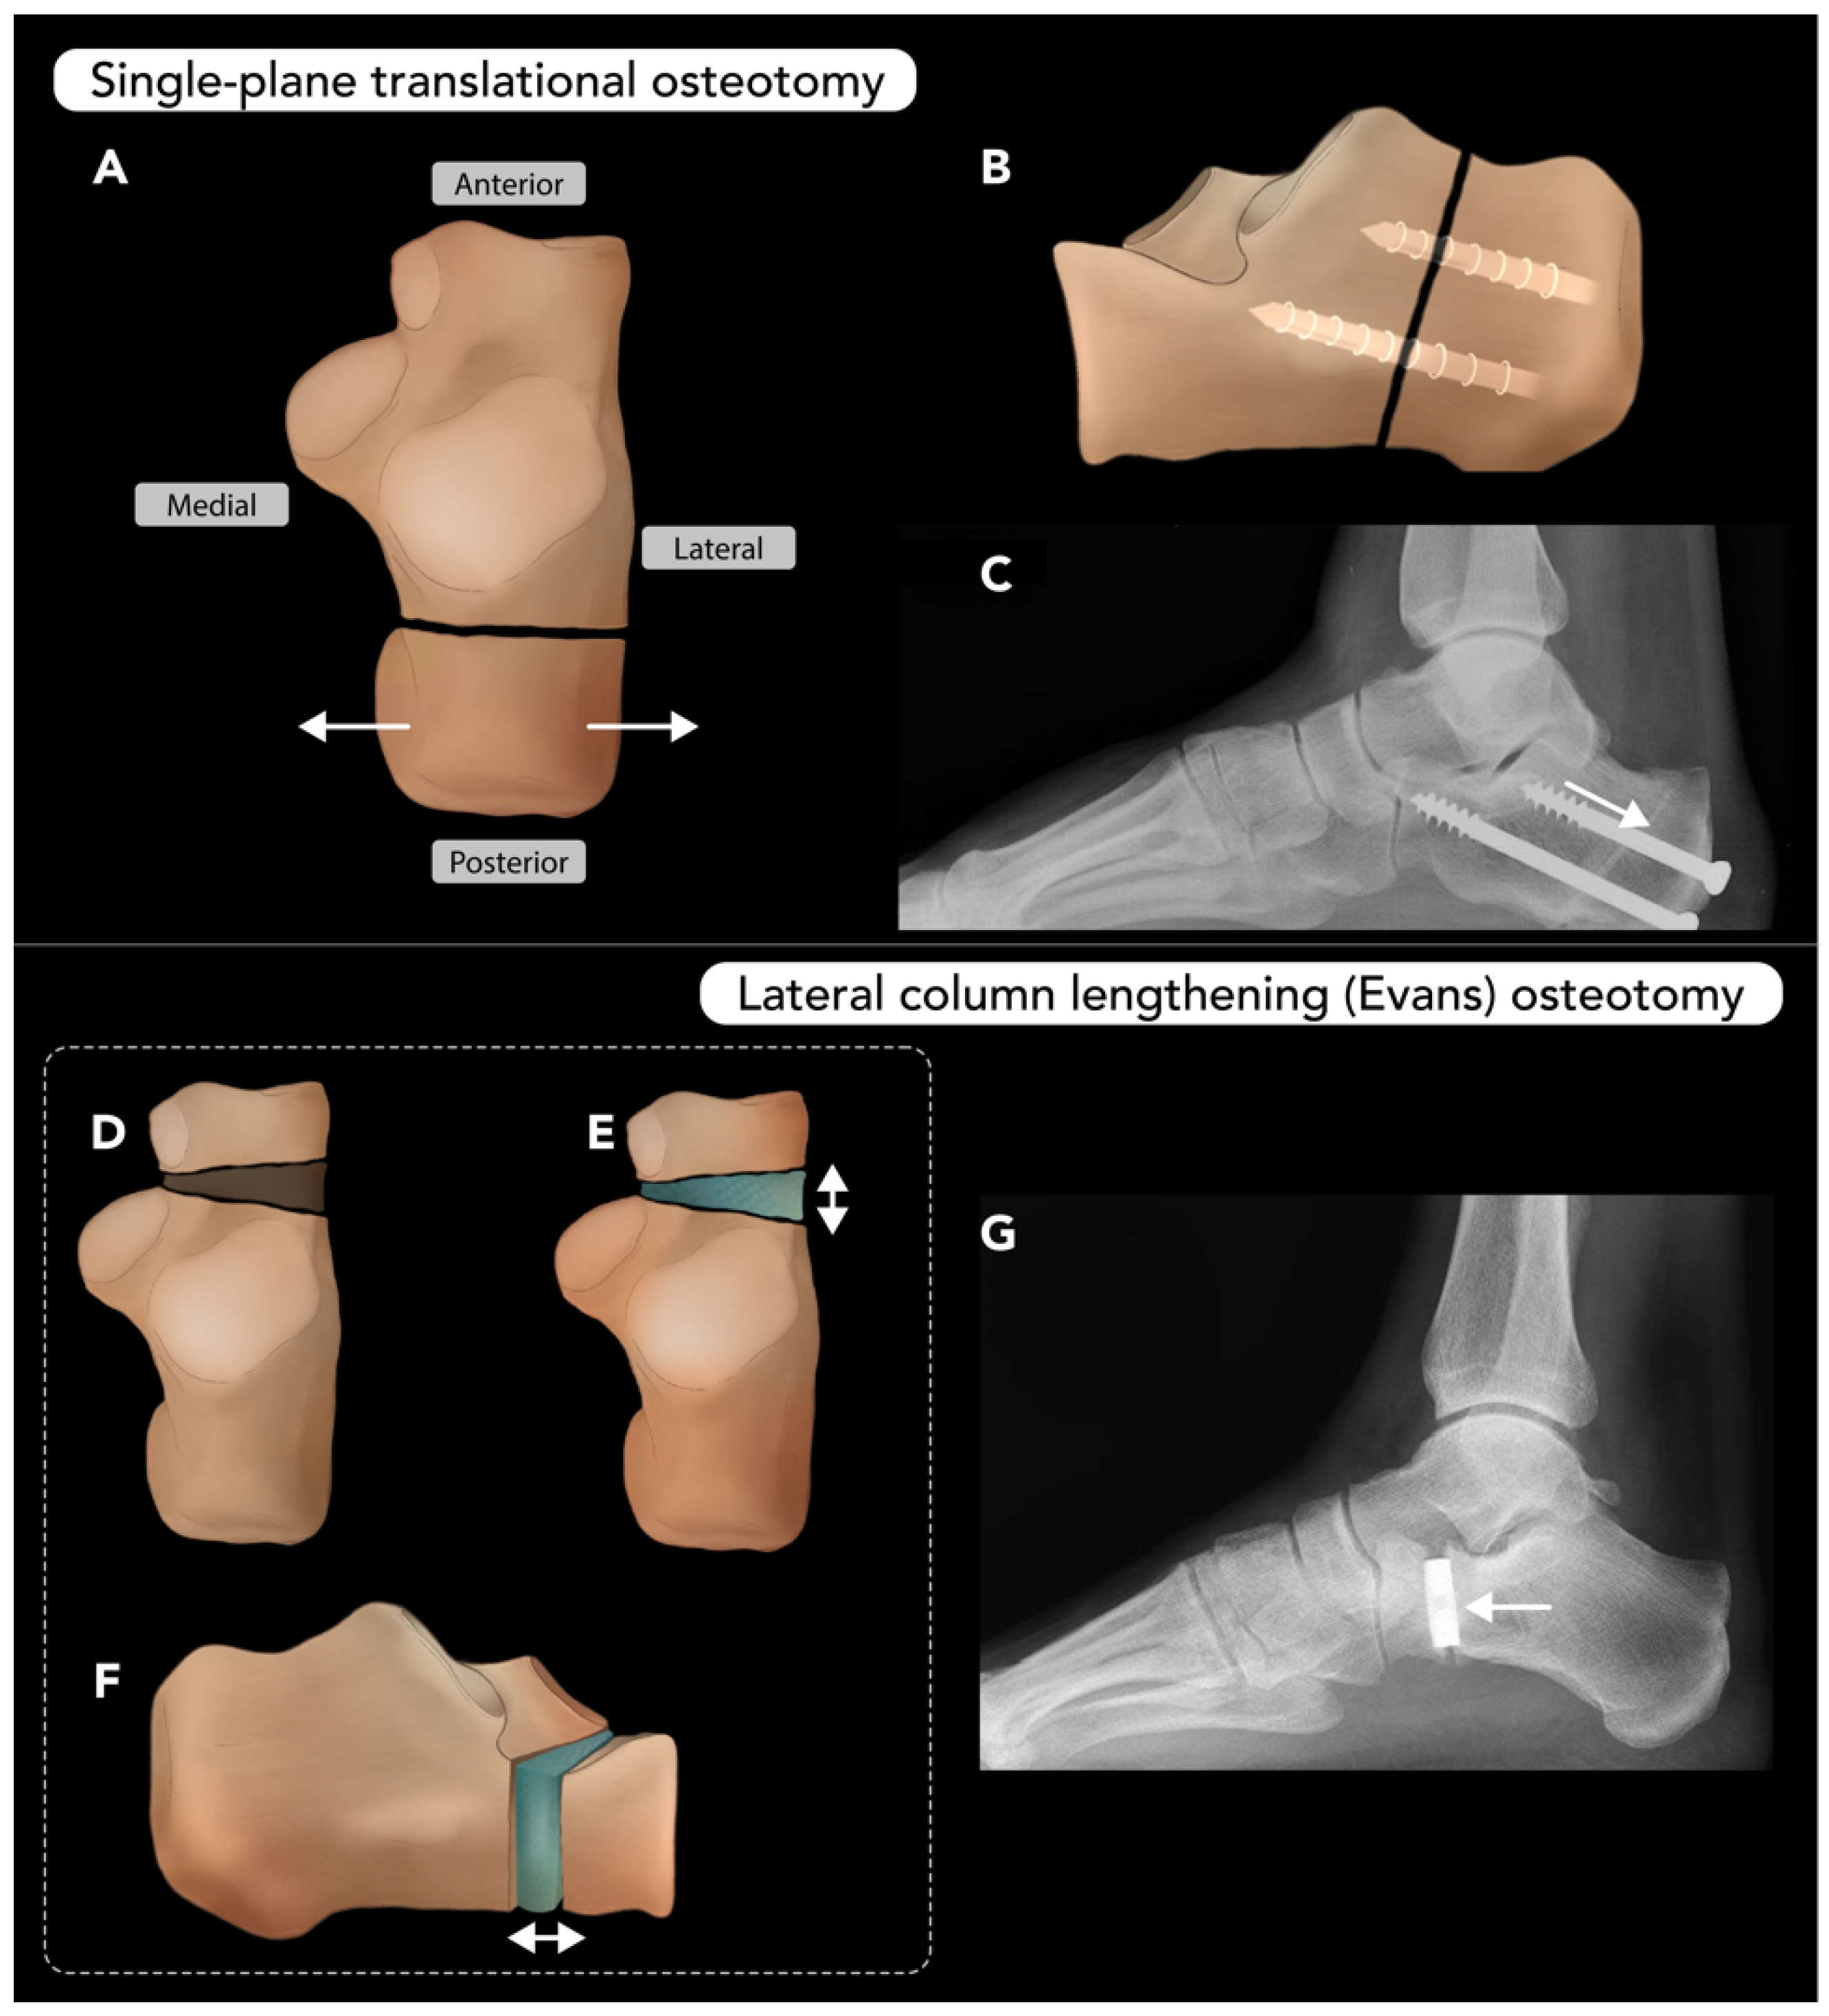

2.3.3. Calcaneal Osteotomy